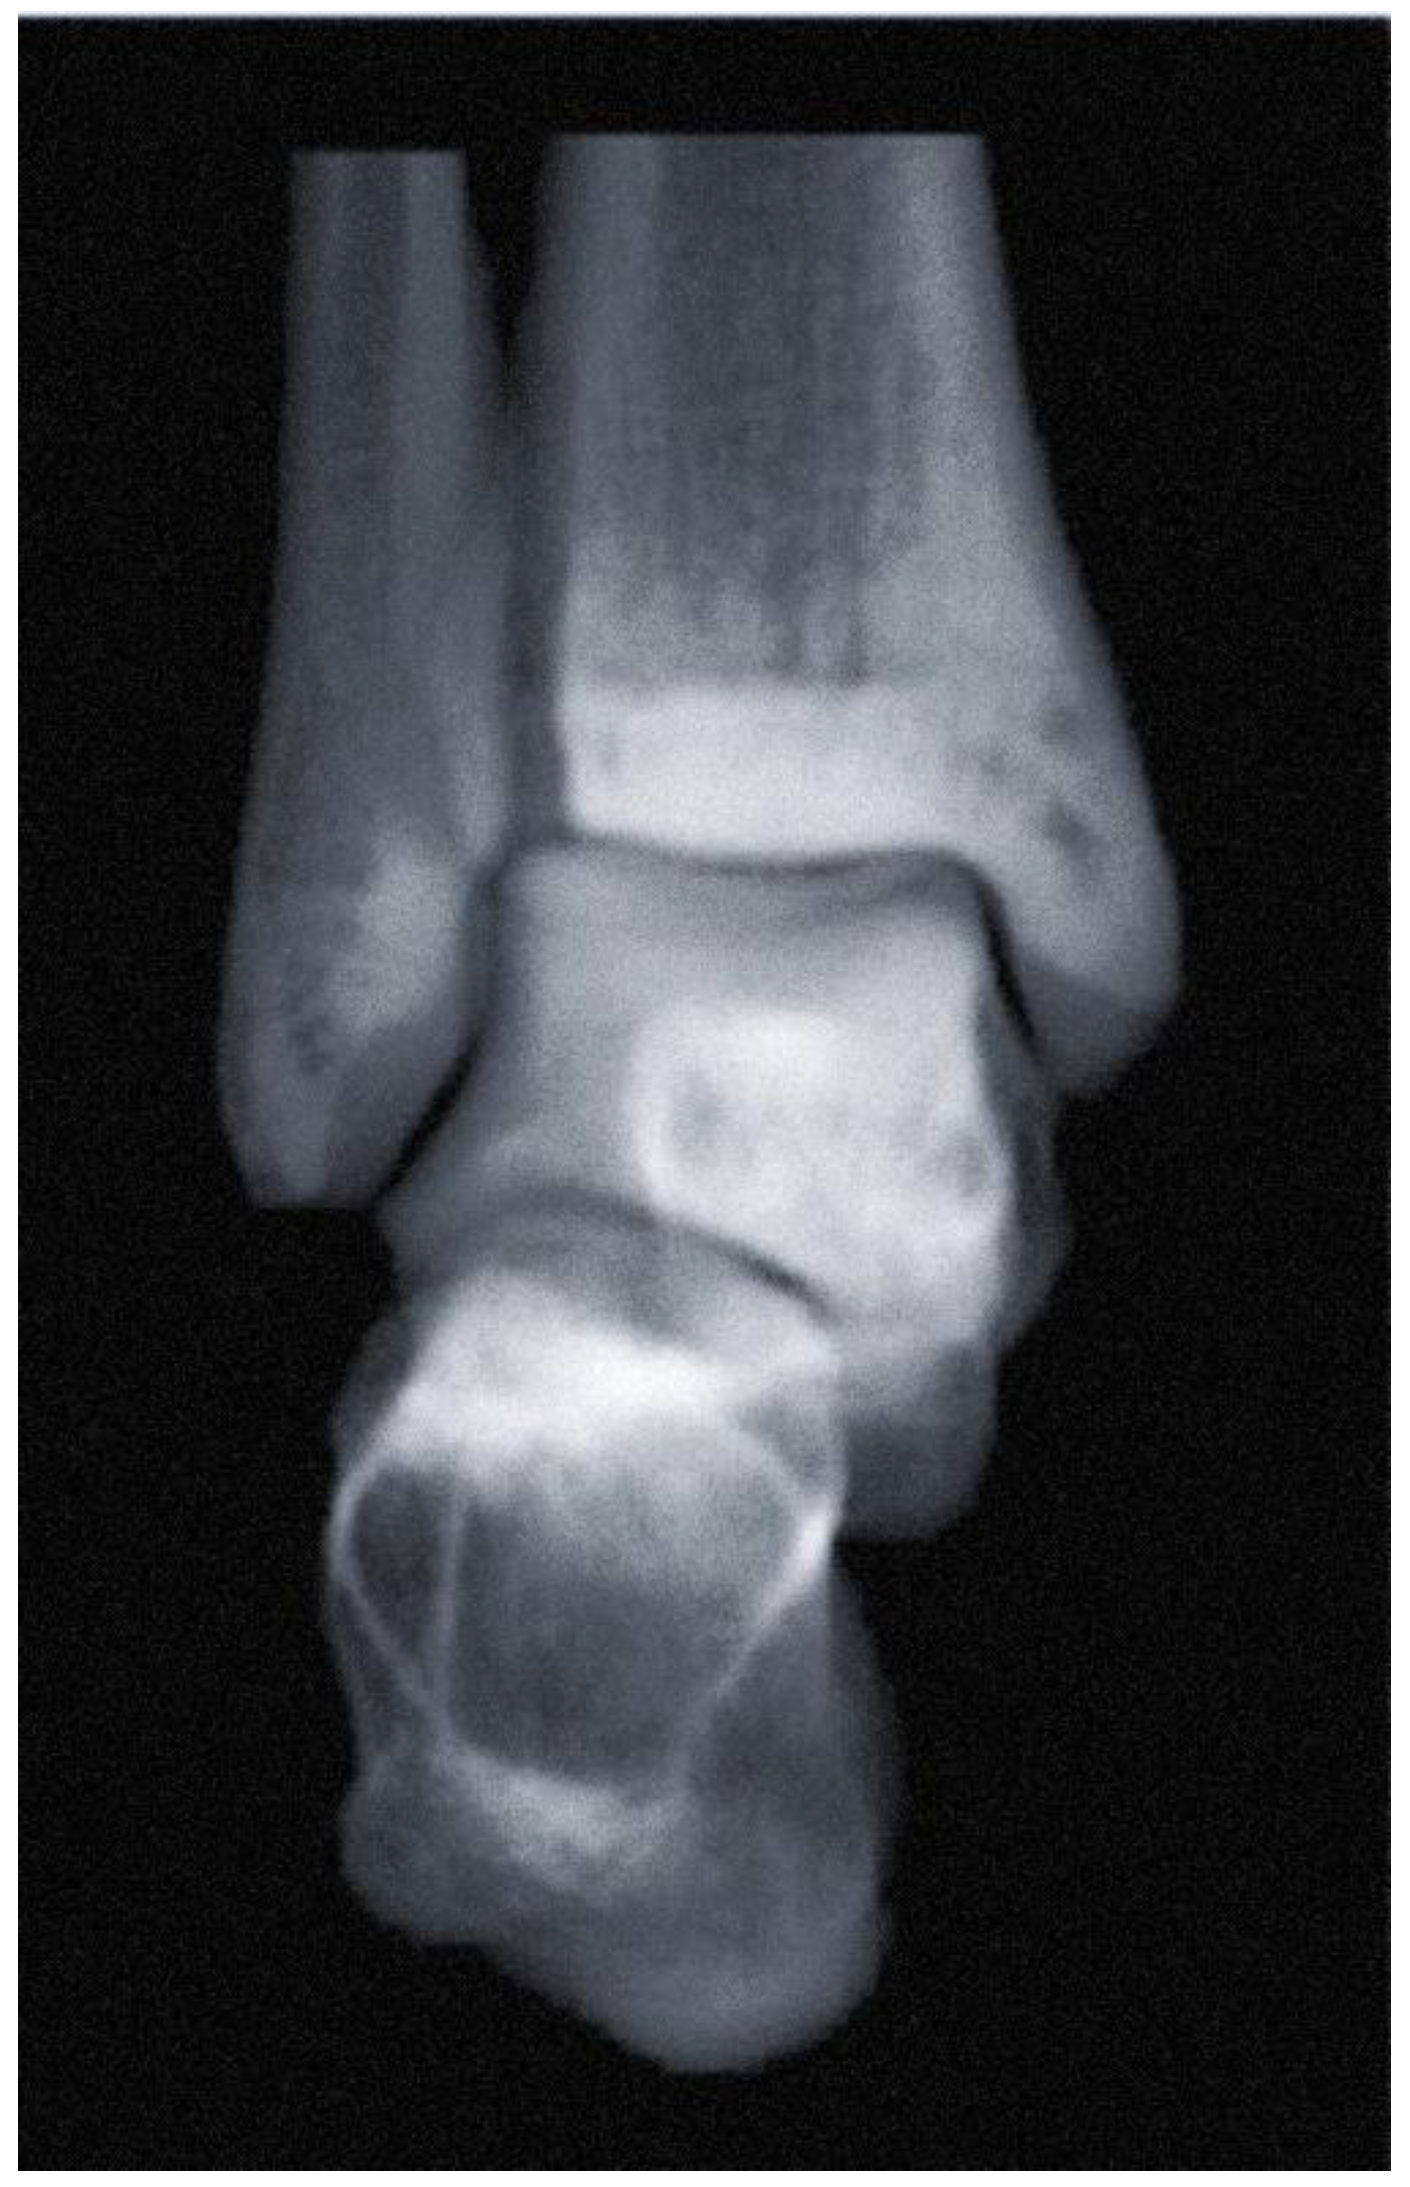

- Ankle Osteoarthritis